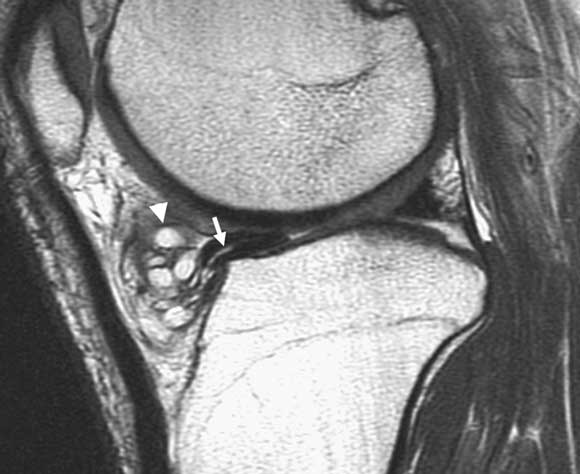

Case study 1 — knee pain

A 50-year-old, mainly sedentary, male ex-footballer with gradual onset knee pain. There are no mechanical symptoms such as locking. He has well-localised tenderness on the medial joint line and a mild effusion. He gets medial knee pain on squatting but can move his knee from full extension to full flexion without any catching (equivocal or negative McMurray’s test). Differential diagnosis: Medial compartment osteoarthritis and/or degenerative posterior horn tear of the medial meniscus. Imaging options: A plain x-ray series (with weightbearing views) is essential to determine the presence and degree of any degenerative change in the medial joint compartment, which dramatically affects management. At his age, severe degenerative changes may indicate definitive surgery, such as total or unicompartmental knee replacement. If the x-ray shows no degenerative changes, the likelihood of a clinically-relevant medial meniscal tear is significantly increased, as is the likelihood of knee arthroscopy giving an excellent result. It is in this scenario (clinical picture compatible with meniscal tear, but diagnosis uncertain) that an additional test such as magnetic resonance imaging (MRI) becomes valuable,18 as a confirmed diagnosis would alter the management (see Figure). If the x-ray shows moderate degeneration of the medial compartment, but not to the degree of needing major surgery (yet), then the recommended management of this patient is generally to persist with conservative treatment (glucosamine, moderate activity, hyaluronic acid injections). In this situation, surgical management is unlikely to be indicated as there is no mechanical restriction of movement,19 which means an MRI is probably an over-investigation. |